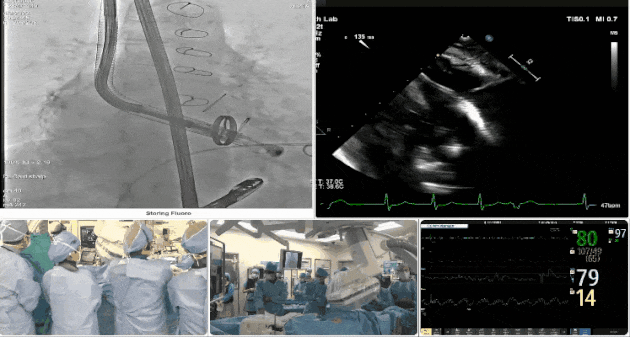

術中TEE觀察夾持件的位置

術后DSA

術后超聲評估瓣膜穩定性良好,無瓣周漏

手術過程

術者采用經右側頸靜脈入路的方式將輸送器送入患者心臟內,在TEE及DSA引導下調整輸送器頭端角度,使得輸送器與三尖瓣瓣環平面垂直。在輸送器進入右心室后釋放室間隔錨定裝置,而后釋放瓣葉夾持件(2個耳片結構)成垂直狀態。在TEE及DSA確定夾持件固定至三尖瓣葉根部且位于右室側后釋放人工瓣心房側盤片。隨后調整瓣膜同軸性以及室間隔錨定件位置(貼合室間隔),前推藏針管并固定,進而釋放室間隔錨定裝置,并再次確認瓣膜位置、穩定性及同軸性,合攏輸送鞘后撤出輸送器,最終順利完成LuX-Valve Plus人工三尖瓣瓣膜的植入。